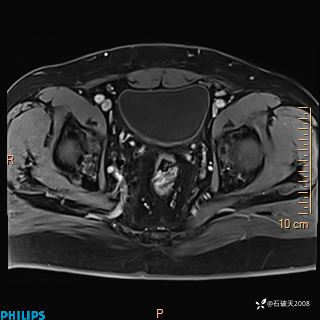

现病史:7个月前患者因骶尾部占位就诊于北京大学人民医院,MRI示:骶骨右侧及右骶前占位,考虑骨巨细胞瘤可能,动脉瘤样骨囊肿可能,神经源性肿瘤待排。行手术治疗,术后病理回示:XXXXX。术后给予对症治疗,具体不详,恢复良好。近几个月反复出现发热,伴骶尾部不适,多次住院给予对症治疗,2天前患者无明显诱因再次发热伴骶尾部不适,无大小便失禁,为求进一步治疗,遂门诊来我院,在门诊初步检查后,以“骶尾部肿物”为诊断收入我科。入院来患者神志清,精神一般,饮食睡眠可,大小便无明显异常,体重无下降。

2023年3月份MRI影像

增强轴位